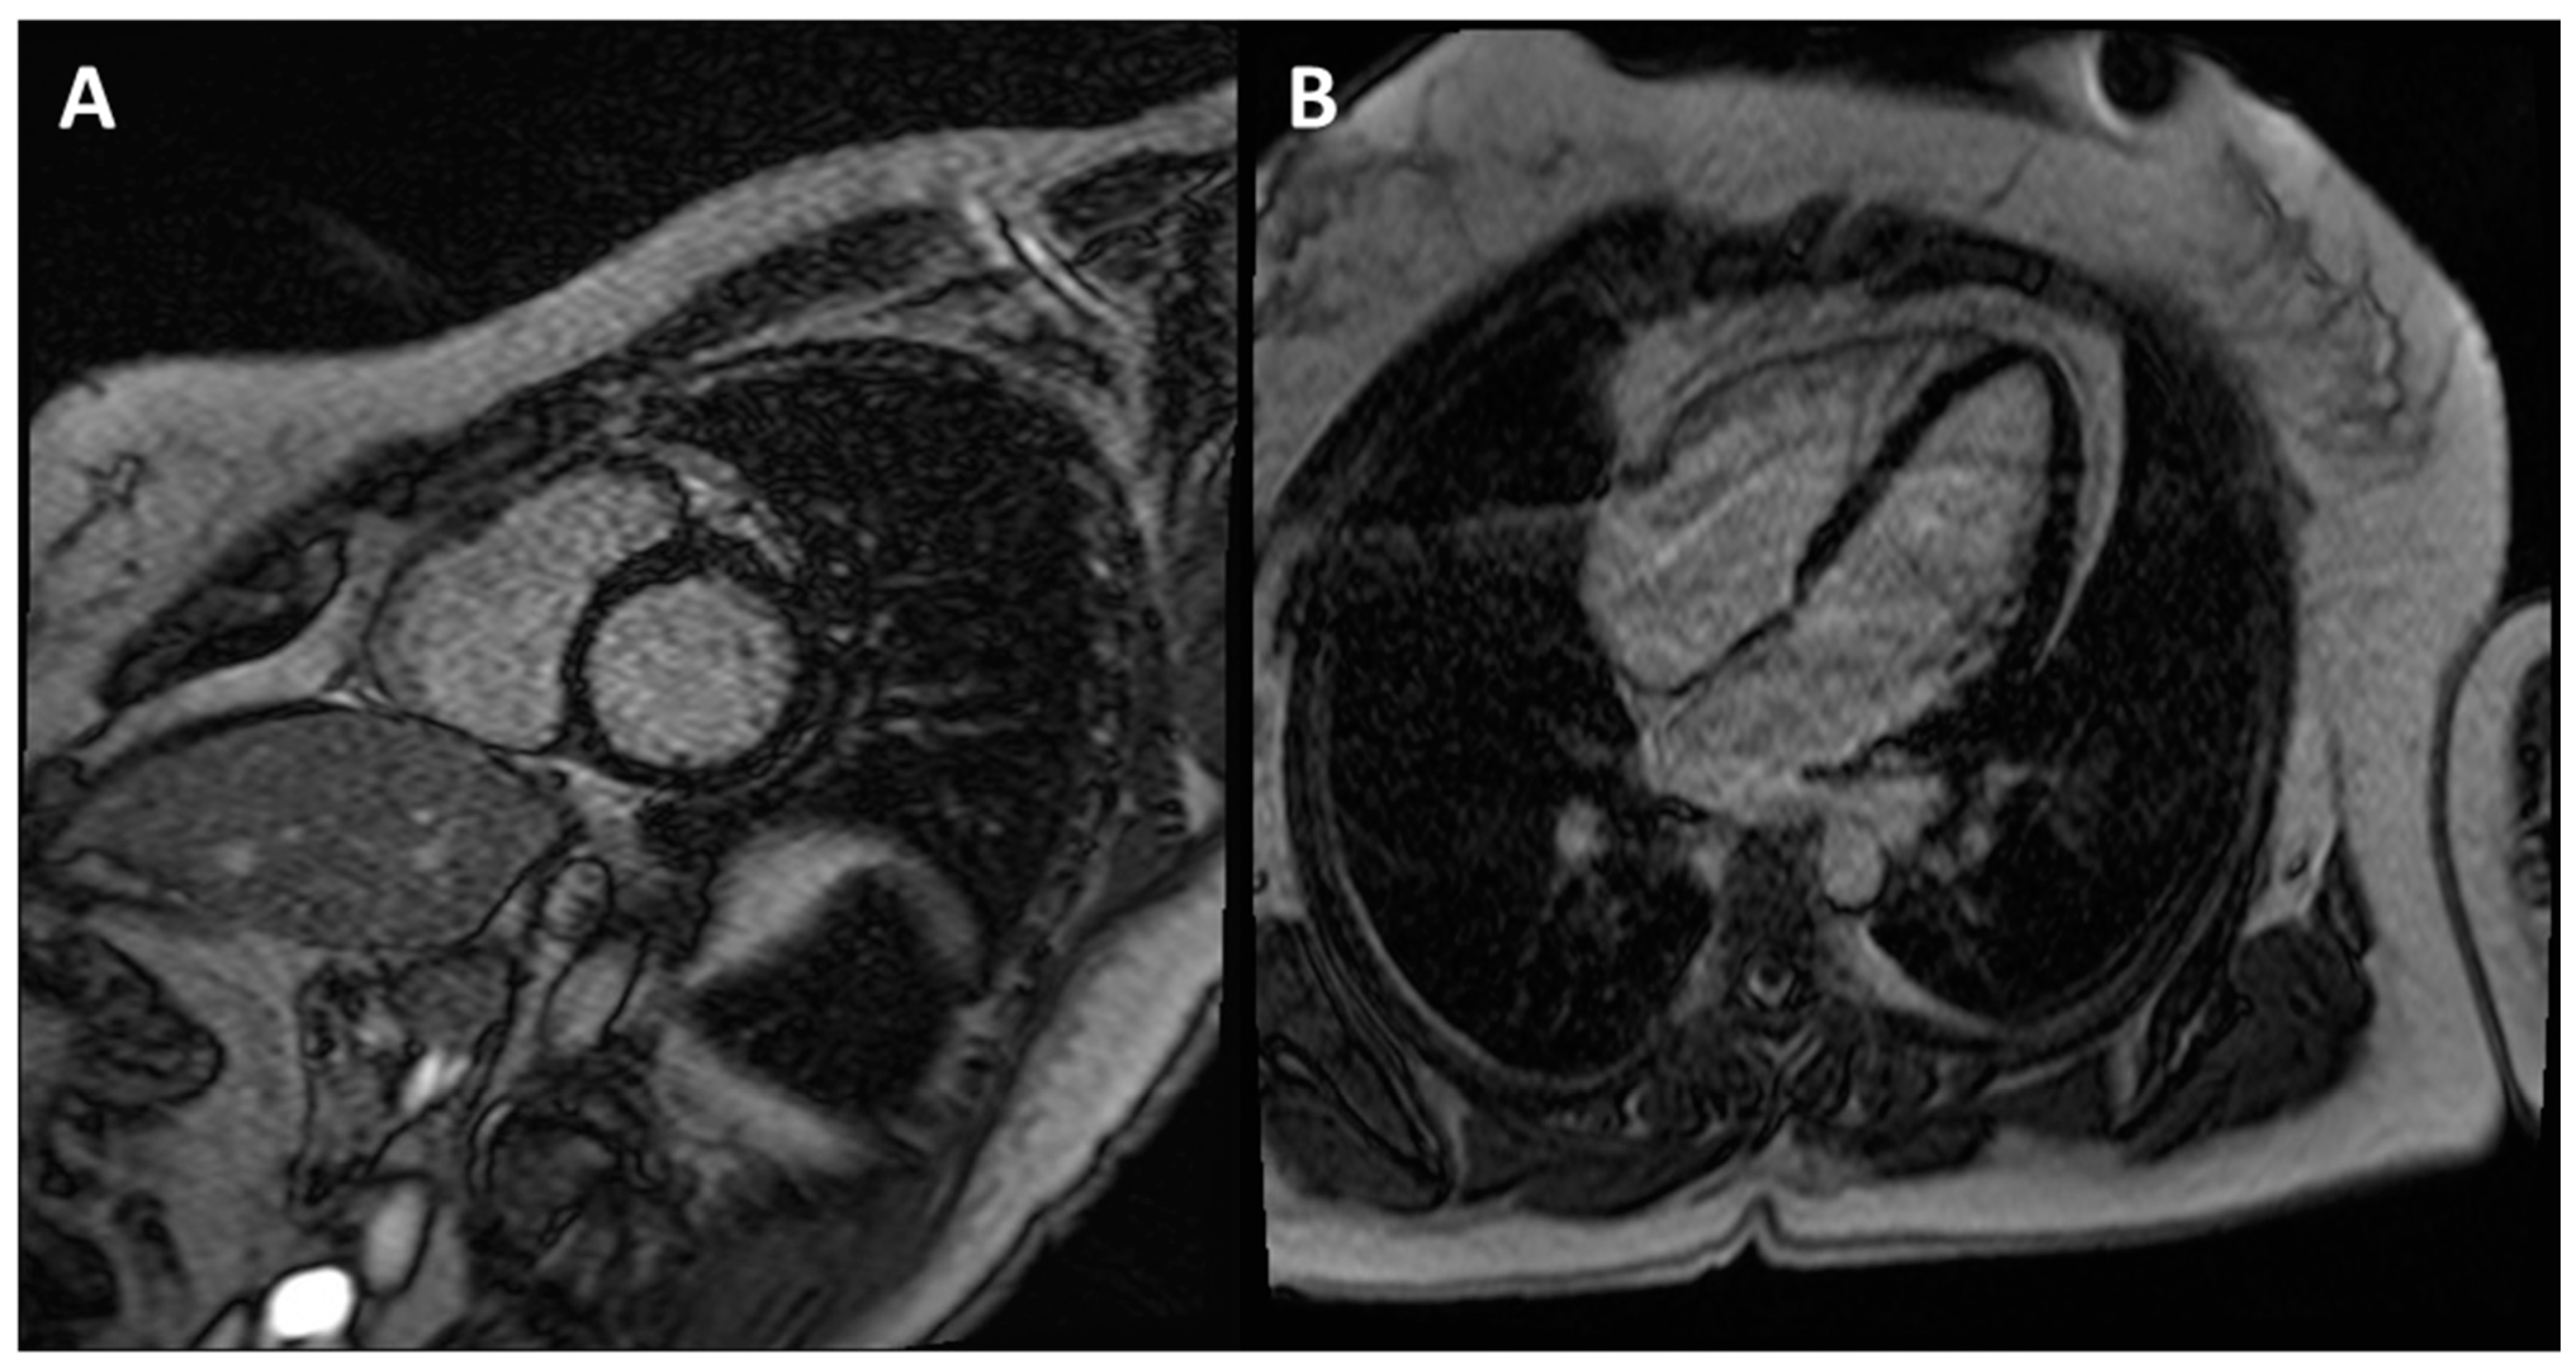

Figure 5.

CE-CMR images in patients with ACM without RV morpho-functional abnormalities and LGE. (A) Short axis two-chamber view. (B) Long axis four-chamber view. (C) RV electroanatomic mapping depicting an epicardial scar on the RV free wall. Unipolar voltage map showing low voltages consistent with an epicardial scar. (D) Bipolar voltage map showing normal voltages.